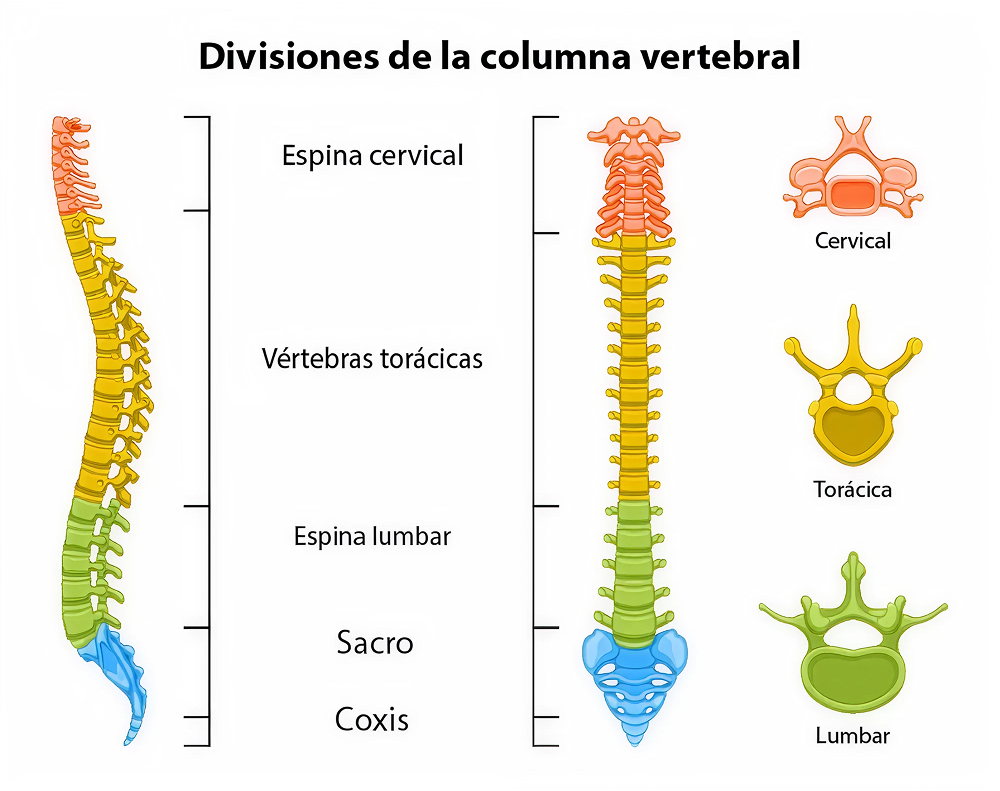

¿Qué significa “columna cervical”?

La columna cervical corresponde a las primeras vértebras de la espalda (generalmente entre C1-C7) que estabilizan y dan movilidad al cuello, mientras protegen la médula espinal y las raíces nerviosas que salen hacia los brazos. Cuando aparecen lesiones o degeneración en esta región, pueden producirse dolores de cuello, irradiación a los brazos, debilidad, hormigueo, alteraciones de equilibrio o incluso daño de la médula espinal.

¿Qué es la columna lumbar?

La columna lumbar corresponde a las vértebras bajas de la espalda (normalmente L1-L5). Esta región, sometida a gran carga mecánica, permite la movilidad del tronco, soporta el peso corporal y protege las raíces nerviosas que se dirigen hacia las piernas y la estructura pélvica. Cuando la anatomía o la función se alteran, puede surgir dolor lumbar, irradiación al miembro inferior, entumecimiento, debilidad, alteraciones de la marcha o pérdida de control de esfínteres, en casos severos.